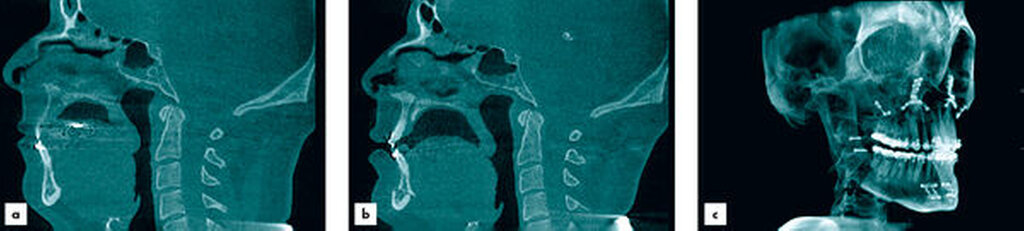

Anders als in der Leitlinie, in der die Fernröntgen-Seitaufnahme zur Diagnostik der OSA als Standard angegeben wird, sehen wir dies als überholt an. Die digitale Volumentomografie (DVT) ermöglicht nicht nur eine bessere Beurteilung der skelettalen Situation des gesamten Gesichtsschädels, sondern auch die dreidimensionale Beurteilung des Posterior Airway Space. Um eine suffiziente Reproduzierbarkeit und Vergleichbarkeit der Daten zu erlangen, muss streng auf die Zungenposition geachtet werden. Dies entspricht auch den Erfahrungen aus der eigenen Patientenklientel [Hochban, 2017; Naujokat et al., 2018; Lindorf et al., 2021; Kochel et al., 2013; Heiland et al., 2020].